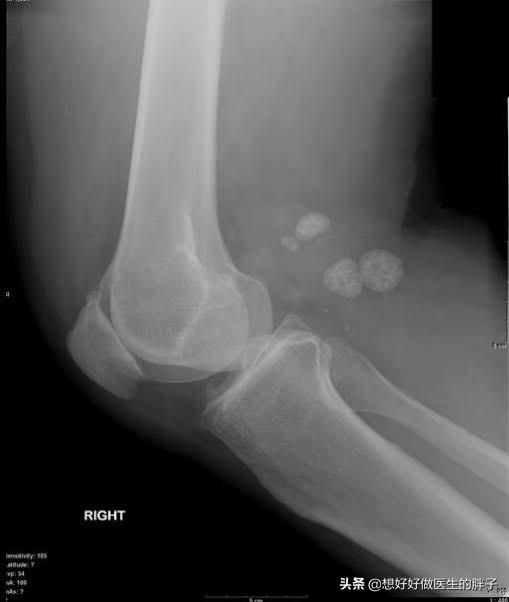

关节内游离体,也叫关节鼠

常见的导致关节内存在游离体的病因,多数是由于关节受到外伤以后,关节腔的软骨脱落到了关节腔内,有的时候这些脱落的软骨会慢慢的被磨损吸收掉,而有的时候这些软骨会慢慢变成钙化形成游离体。(下图就是软骨破裂的影像学资料)

另外还有一种比较常见的情况是关节腔的滑膜软骨瘤病,这种情况就类似于患者的关节腔内滑膜变成了一个巢穴,从巢穴内不停地往关节腔内生产软骨样的游离体。(下图为滑膜软骨瘤病的影像学资料)

由于这些游离体在关节腔内,会发生位置的变化,所以也被称之为关节鼠,有的时候这些游离体会卡别在关节腔内,造成患者出现打软腿的症状,如果卡别的比较急骤的时候,患者就会出现明显的疼痛。

一般情况下,关节腔内游离体的诊断,进行膝关节x线检查就可以明确了。(下图在膝关节后方的都是游离体)

关节腔内的游离体如果诱发患者出现打软腿的情况不是特别的频繁,患者又没有主观的意愿想要将游离体取出来,可以保守治疗。

而如果游离体诱发患者出现反复的,频繁的关节打软腿,同时伴有剧烈的疼痛,有一些患者会出现关节腔的积液,那么需要进行关节镜手术治疗将游离体取出来。